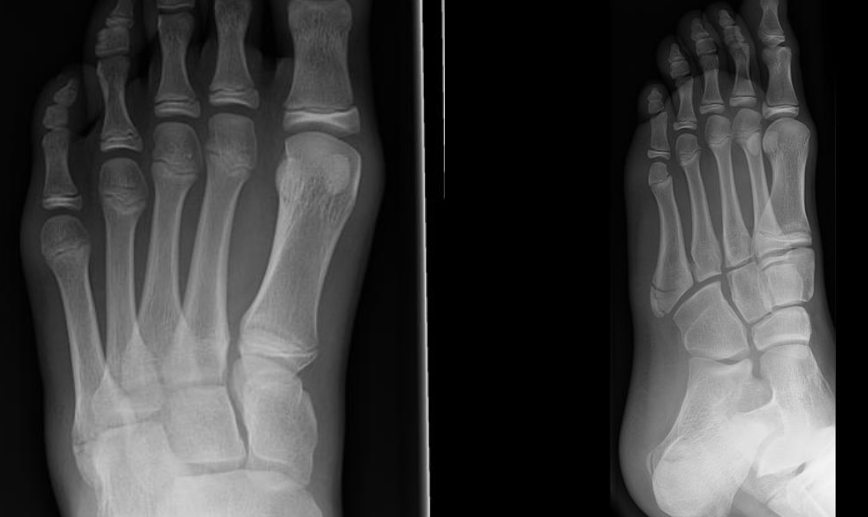

A 13-year-old male presents to the urgent care after rolling his left ankle while playing soccer. He now has pain and swelling around the outside of his foot and can’t bear weight on it. X-rays are taken and shown below:

Metatarsal Madness

A 57-year-old female presented to the emergency department with complaints of severe pain in her right foot after twisting her ankle earlier today. She denies any numbness or tingling, but has had difficulty walking due to the pain.